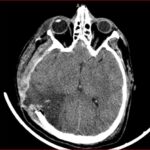

Figura 4. TAC de encéfalo estudio simple y con contraste (26/09/2022). Cambios quirúrgicos por craneotomía temporoparietal derecha, persiste herniación secundaria del parénquima encefálico, con restos hemáticos, fragmentos óseos y marcado edema de tejidos blandos, no se ponen en evidencia colecciones tras la administración de contraste endovenoso.

Figura 5. TAC de encéfalo simple (13/10/2022). Herniación transcraneana que retrae los ventrículos laterales. Marcada hipodensidad en toda la sustancia blanca profunda de parénquima cerebral derecho, que se extiende hacia las regiones cortico subcortical homolateral, en menor medida también se ve afectación de la sustancia blanca profunda contralateral.

Figura 6. TAC de encéfalo simple (13/12/2022). Disminución de la herniación transcraneana. hipodensidad cortico subcortical parietal derecha que retrae el hasta posterior del ventrículo lateral homolateral.